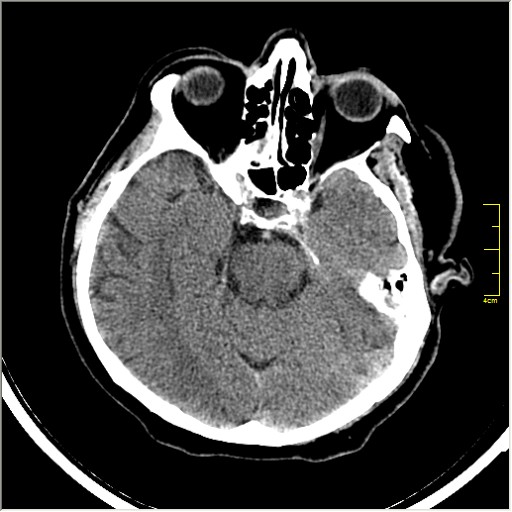

Пациентка Д. 64 года. Поступила с диагнозом ОНМК ???, жалобы на онемение и слабость в левой половине тела.

Ответ: Обратите внимание на правую среднемозговую артерию (MCA); М1 сегмент гиперденсен; сравните с другой стороной.

Этот признак называется [Dense MCA sign]; за счёт наличия тромбоза в её просвете. Этот признак является одним из ранних указующих КТ признаков при ишемическом инфаркте головного мозга. Более подробно об этом вы можете прочитать здесь: http://www.radiologyassistant.nl/en/483910a4b6f14.